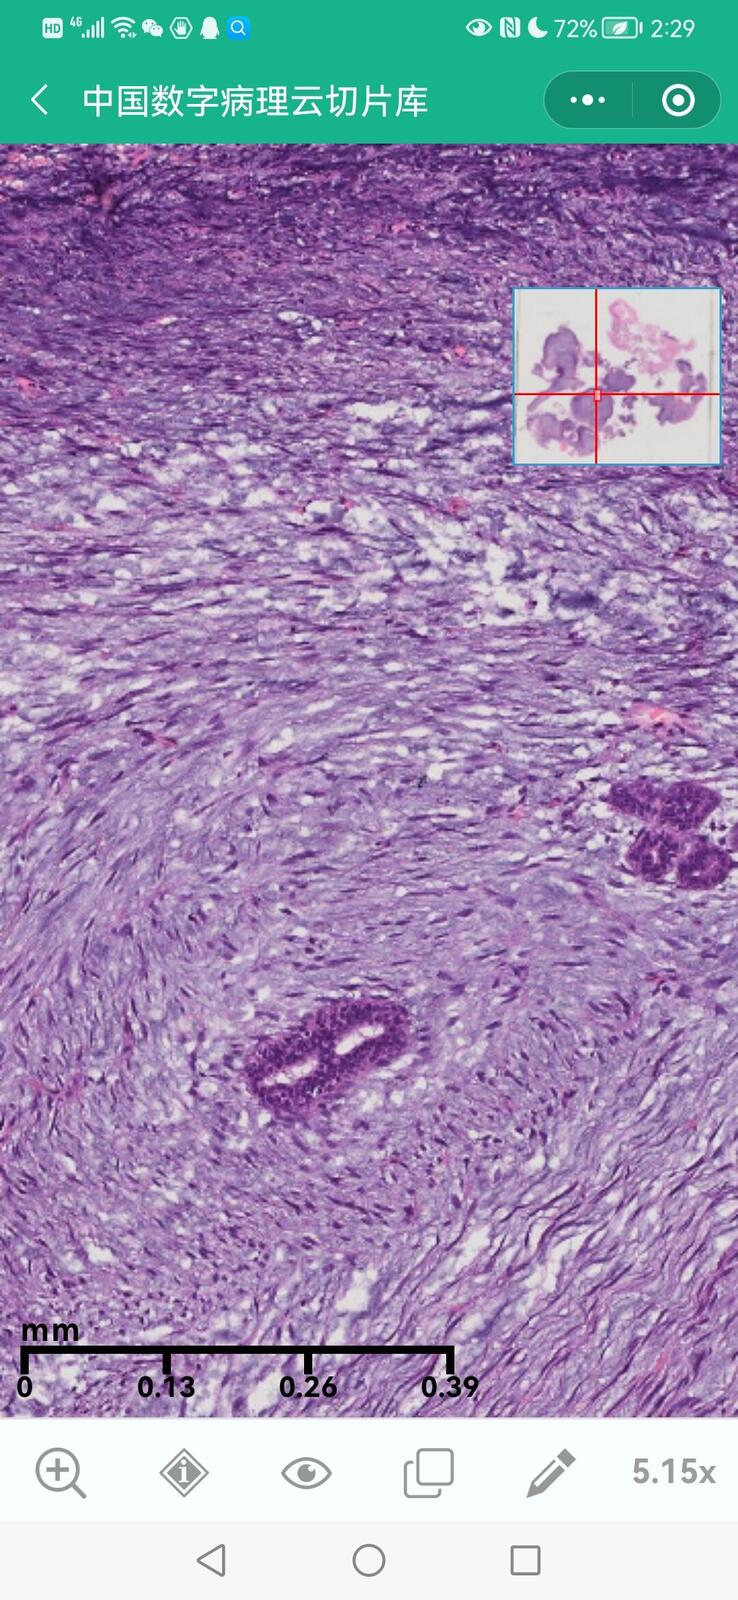

乳腺叶状囊肉瘤